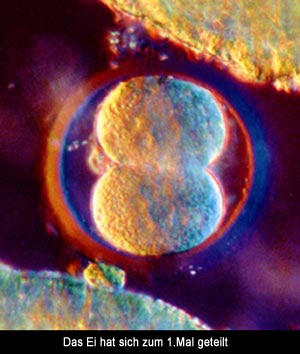

7) Teilungen des Ei

Anschließend werden die Außenwände

der Kerne aufgelöst, und alles verschwindet im Plasma der Eizelle.

Nur einige Stunden nachdem die Kerne verschmolzen sind, teilt sich das

Ei zum erstenmal. Es hat jetzt 2 Zellen, jede von ihnen enthält die

Erbanlagen von Mutter und Vater. Diese Teilung wiederholt sich alle 12-15

Stunden. Wenn die Zygote etwa 16 Zellen besitzt, verformt sie sich zur

hügelig-rauen "Morula", die ihren Namen von der ähnlich

aussehenden Maulbeere hat und etwa 0,2 Millimeter groß ist.